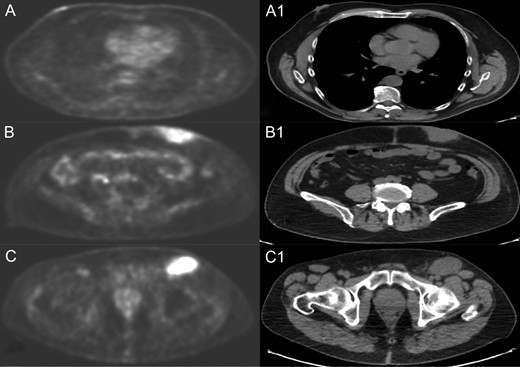

A positron emission tomography (PET) with CT-scan reconstruction showed hyper metabolic at the right breast nodule of 1.8 cm (SUV 3.7), at the left abdominal mass of 6 cm (SUV 9.37) and at superficial (SV 9.6) and deep (SUV 8.5) inguinal lymph node (Fig. 1).

PET and CT scan of right breast nodule (A and A1), left abdominal mass (B and B1) and left inguinal lymph node (C and C1).